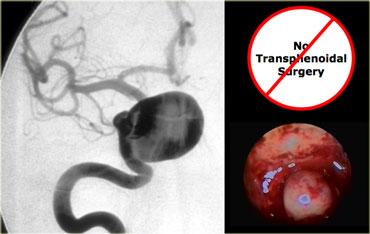

Các hình ảnh này mô tả phẫu thuật cắt bỏ u tuyến yên đại tuyến qua đường xuyên bướm (transsphenoidal resection).

Sau khi phần sàn xương của hố yên được lấy bỏ, màng cứng (dura) được rạch bằng đường rạch hình chữ thập.

Do áp lực phía trên màng cứng lớn hơn áp lực phía dưới, khối u đại tuyến sẽ tự thoát ra vào xoang bướm (sphenoid sinus).

Chụp MRI trong mổ được thực hiện trong một bối cảnh thử nghiệm để xác định xem phẫu thuật viên thần kinh có lấy bỏ thành công toàn bộ khối u hay không.

Do việc sử dụng đường phẫu thuật này có trường nhìn hạn chế, điều quan trọng là phải biết trước mình đang phẫu thuật trên tổn thương gì.

Như chúng ta sẽ thấy, có những tổn thương mà bạn không nên phẫu thuật theo đường tiếp cận này!

Bệnh nhân này nhập viện vì tắc nghẽn mũi.

Cô ấy đến gặp bác sĩ tai mũi họng, người đã phát hiện một khối lớn trong mũi và được chuyển đến phẫu thuật viên thần kinh để lên kế hoạch phẫu thuật cắt bỏ nền sọ lớn.

Phẫu thuật viên thần kinh đã từng thấy trường hợp tương tự trước đây và đã kiểm tra nồng độ prolactin của cô ấy.

Kết quả là 4000 (bình thường là 25 hoặc thấp hơn). Sinh thiết qua đường mũi cho thấy u tiết prolactin (prolactinoma).

Sau khi điều trị bằng bromocriptine, khối u co nhỏ lại và không cần phẫu thuật.

Tổn thương nằm một phần trong xoang hang phải và một phần trong hố yên có tín hiệu chủ yếu là đen trên chuỗi xung T1W này.

Nhìn chung, có ba thứ cho tín hiệu đen trên MRI: không khí, xương và dòng máu chảy nhanh. Trong trường hợp này, tín hiệu đen là do dòng máu chảy nhanh trong túi phình động mạch cảnh.

Đây là hình chụp mạch máu (angiogram) tương ứng.

Rõ ràng, đây không phải là tổn thương có thể phẫu thuật qua đường xuyên bướm (transsphenoidal)!